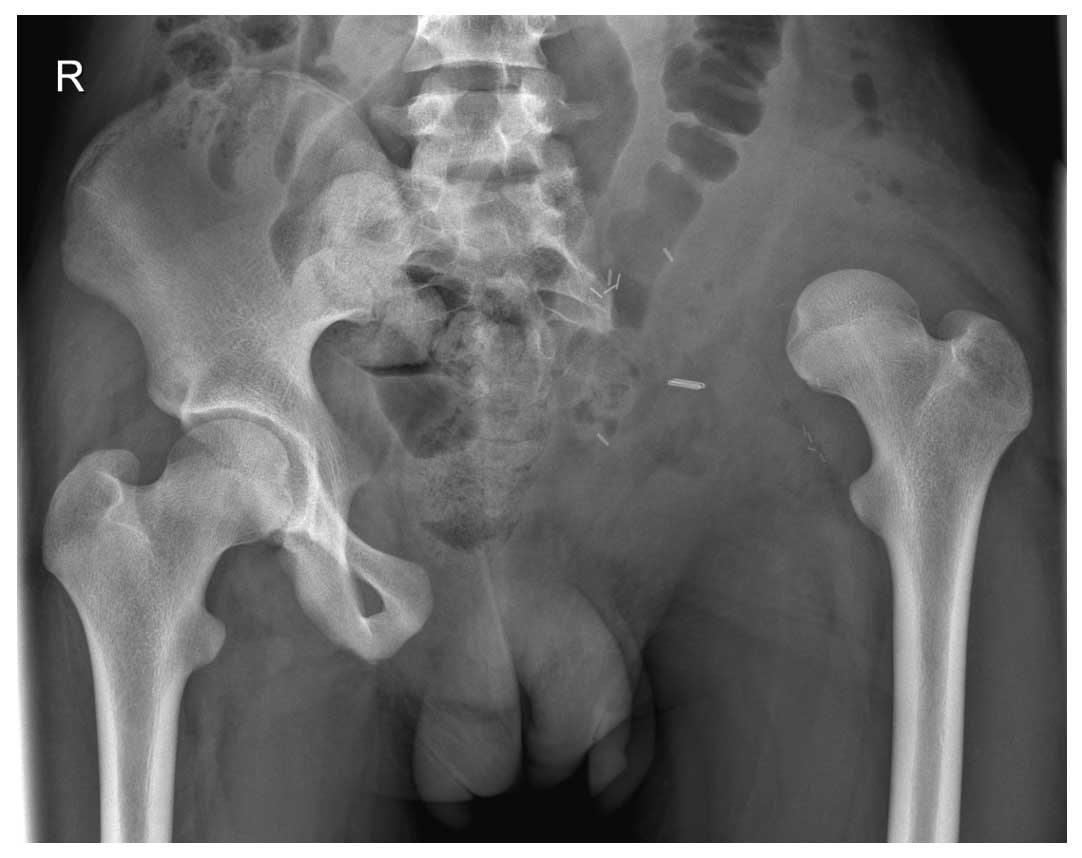

Ameliyat Sonrası: İnternal hemipelvektomi sonrası girdlestone işlemi görülmekte.